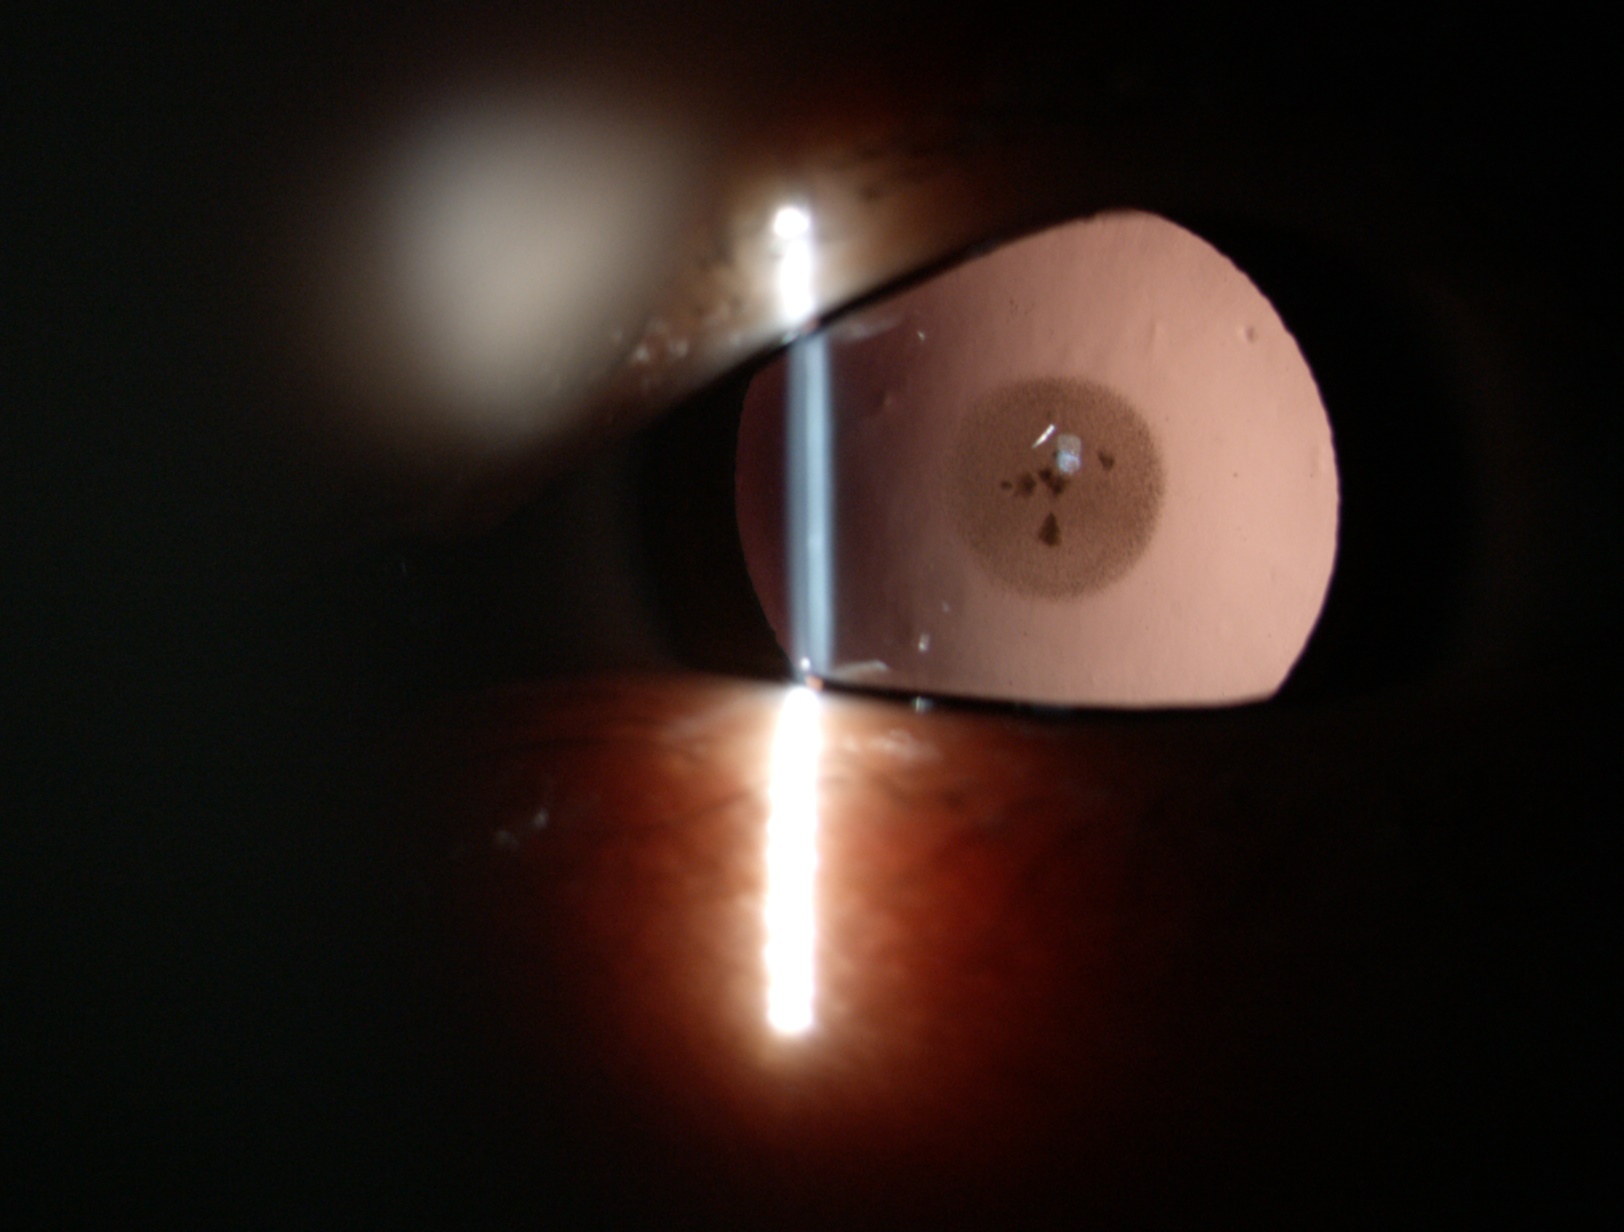

白內(nèi)障癥狀

現(xiàn)在白內(nèi)障手術(shù)都是微創(chuàng)手術(shù),當(dāng)然是手術(shù)切口越小手術(shù)引起的散光越小,對(duì)視力影響也越小。做手術(shù)的超乳設(shè)備穩(wěn)定性越好手術(shù)越順利,出現(xiàn)不必要并發(fā)癥的概率就越小,人工晶體檢查計(jì)算設(shè)備也是非常重要的,直接影響術(shù)后視力,常規(guī)眼球一般經(jīng)典的A/B超和角膜曲率也是比較準(zhǔn)的。